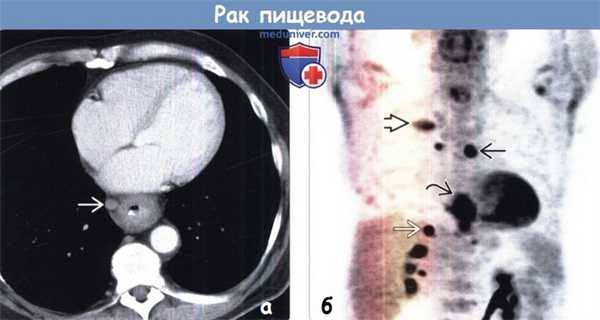

(а) У пациента с аденокарциномой пищевода при КТ с контрастным усилением определяются циркулярное утолщение стенок дистальных отделов пищевода и увеличенный правый параэзофагеальный лимфатический узел.

(б) У этого же пациента при ФДГ-ПЭТ в коронарной плоскости визуализируется интенсивное поглощение ФДГ первичной опухолью, которую сложно отличить от прилежащего параэзофагеального лимфатического узла. Следует отметить наличие лимфаденопатии правой паратрахеальной области и метастазов в заднем отрезке ребра справа и в правом надпочечнике.

6. Методы медицинской радиологии. ПЭТ/КТ:

о По сравнению с КТ позволяет точнее определить проксимальную и дистальную границу опухоли, что важно для планирования лучевой терапии

о По сравнению с ПЭТ позволяет точнее проводить стадирование регионарных лимфатических узлов благодаря установлению локализации очагов поглощения ФДГ вблизи первичной опухоли

о В 5-40% случаев позволяет обнаруживать не выявленные до этого отдаленные метастазы

о При первичном стадировании позволяет в 1,5-8% случаев выявлять синхронное первичное злокачественное новообразование

о Высокая чувствительность при определении рецидивирования опухоли или выявлении метастазов после проведенного лечения

о Позволяет на раннем этапе определить эффективность неоадъювантной терапии

о ПЭТ /КТ используется для стадирования, рестадирования и выявления синхронной злокачественной опухоли